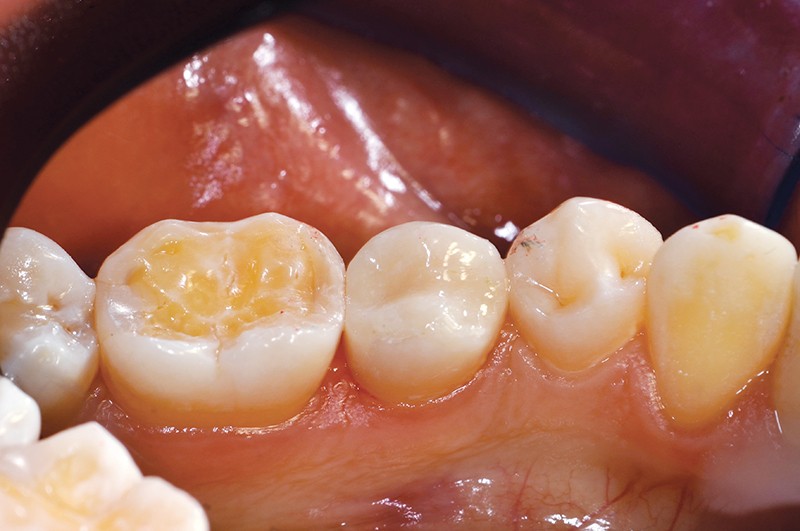

Les ciments verre ionomère (CVI) semblent occuper une place croissante dans nos choix thérapeutiques. Leurs qualités (biocompatibilité, étanchéité, prévention de la carie et des récidives) ont permis de compenser les piètres qualités mécaniques des CVI basse viscosité d’il y a 40 ans (résistance à la flexion et à l’abrasion), et d’évoluer. L’apparition de CVI Haute Viscosité « Imprégné-Protégé » semble élargir encore leurs indications, surtout dans le cadre fréquent du patient à risque carieux élevé. Obtenir un résultat clinique optimal, demande de comprendre le processus de prise et de le respecter lors des protocoles mis en œuvre.

Les ciments verre ionomère offrent biocompatibilité, étanchéité, prévention des récidives carieuses, et bonne alternative aux matériaux traditionnels, surtout dans le contexte du patient cario-actif.